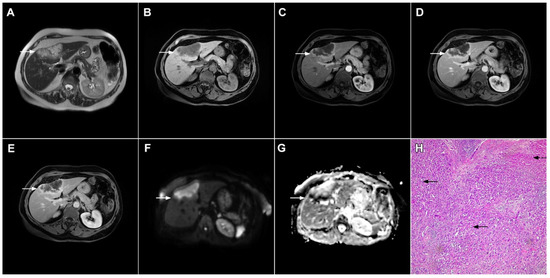

The most common postcontrast enhancement seen in SHLM is ring enhancement in the arterial phase with minimal central enhancement in the delayed phases [68]. This vascular behavior could be explained by the fact that metastatic tumors parasitize the surrounding blood vessels, creating the ring appearance of blood supplying the most vascularized outer parts of the tumor [25]. On the contrary, in mICCs arterial ring enhancement is commonly followed by progressive central enhancement [5,29]. Nevertheless, previous studies have shown that the enhancement characteristics of these two tumors may overlap. Although the central T2-weighted hypointensity and bile duct dilatation proximal of the tumor are considered to be typical for mICC, they can also occur in liver metastases [68]. In such cases, other imaging features, including shape of the lesion, capsular retraction, and portal lymphadenopathy, are suggestive of mICCs [17]. Recent studies have stressed the importance of imaging appearance in DWI for the differential diagnosis. Accordingly, Park et al. found the “target sign” to be a significant predictor of mICC as it was present in 75% of mass-forming ICCs in their study population [16]. Even though all these findings are more frequent in mICC, they can also be observed in SHLM, especially colorectal cancer (Figure 16) [74,75]. In conclusion, considering that both the imaging and pathohistological features of mICC and SHLM significantly overlap, the first step in the diagnosis of mICC should be the exclusion of extrahepatic malignancies, especially colorectal carcinoma.

Figure 16.

Solitary hypovascular liver metastasis in a 59-year-old woman. A slightly hyperintense lobulated lesion (arrow) with capsular retraction is seen in liver segments VI and VII in the T2-weighted image (A). The tumor (arrow) is hypointense in the plain T1-weighted image (B) with a slight peripheral enhancement in the arterial phase (C) and a progressive central enhancement in the portal venous (D) and delayed phases (E). In the DWI (F) and corresponding ADC map (G), the tumor (arrow) shows targetoid appearance. Hematoxylin and eosin (H&E) staining showed well-differentiated adenocarcinoma cells of intestinal type (dashed arrow), and normal liver parenchyma adjacent to the metastasis (arrow); original magnification ×40 (H).

3.2.2. Atypical Forms of Hepatocellular Carcinoma

Scirrhous HCC

Scirrhous HCC is a rare variant of HCC characterized by rich intralesional fibrotic stroma with incidence of 4.6% among all HCC cases [76]. Scirrhous HCCs are usually seen in MRI scans as lobulated T1-weighted hypointense lesions with a heterogeneous signal intensity on T2-weighted images [77]. With regard to its vascular behavior, Kim et al. showed that the most common enhancement pattern was a peripheral rim-like enhancement in the arterial phase with a progressive central enhancement in the portal–venous and equilibrium phase, which is indistinguishable from mICC (Figure 17) [78]. Moreover, in previous studies washout was seen in only 19% of scirrhous HCC, in comparison to 99.7% of typical HCCs [78]. In addition, similarly to mICC, scirrhous HCC may also cause capsular retraction if it is subcapsular [79]. With regard to the targetoid appearance in the DWI and hepatobiliary phase, both mICC and scirhous HCC can display these imaging features [80]. Therefore, differentiation between scirrhous HCC and mICC represents a real diagnostic challenge, since both lesions have rich fibrous stroma, similar postcontrast behavior, and occur in cirrhotic livers [77]. Concerning different treatment strategies for these tumors, preoperative distinction is very important. In this context, the ancillary feature favoring the diagnosis of mICC include peripheral biliary dilatation, while the presence of a capsule suggests scirrhous HCC [77]. Moreover, the presence of part of the tumor enhancing avidly in the arterial phase favors the diagnosis of scirrhous HCC over mICC [80]. Additionally, Choi SY et al. have shown that mICC more frequently showed T2-weighted central brightness due to the presence of internal necrosis or mucin accumulation [79]. Nevertheless, if the lesion with imaging features of both scirrhous HCC and mICC is seen in the setting of chronic liver disease, according to the Liver Imaging Reporting and Data System (LI-RADS) it is characterized as LI-RADS M and further biopsy is required [81].

Figure 17.

Scirrhous hepatocellular carcinoma in a 68-year-old woman. The axial T2-weighted image (A) shows a moderately hyperintense subcapsular-located lesion in liver segments VI and V (arrow). Note also the capsular retraction. The tumor (arrow) is hypointense in the plain T1-weighted FS image (B), with ring enhancement in the arterial phase (C) and slight progressive central enhancement in the portal venous (D) and delayed phases (E). Hematoxylin and eosin (H&E) staining showed hepatocellular carcinoma (arrow) and normal liver parenchyma adjacent to the tumor (dashed arrow); original magnification ×40 (F).